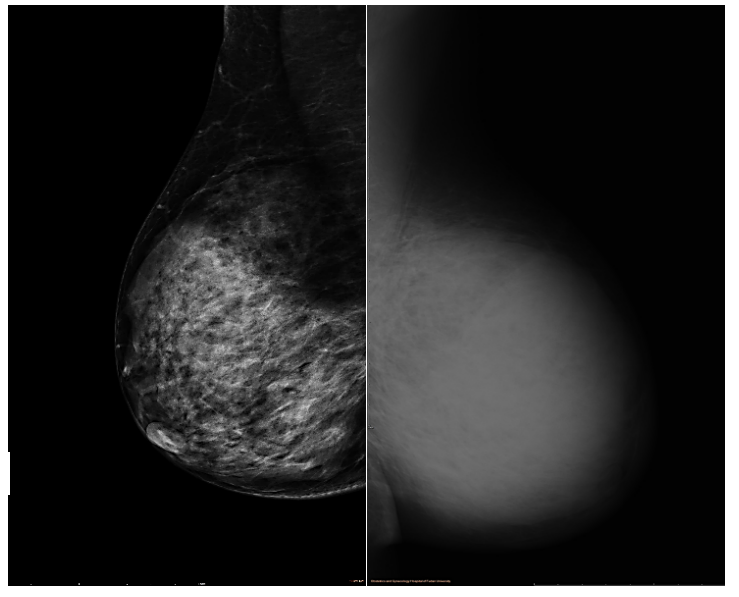

乳腺增强MRI提示左乳皮肤及乳晕增厚,乳头略凹陷,皮下腺体结构紊乱。左乳较右侧明显增大。左乳可见巨大肿块影,大小约12.3cm×6.7cm,T1WI呈等信号,T2WI呈稍高信号,局部DWI呈高信号,ADC减低,增强后明显不均匀强化,时间信号曲线呈平台型。左腋下可见多枚淋巴结影,最大者约2.1cm×1.4cm,BI-RADS 5(图4)。

图4.乳腺增强MRI